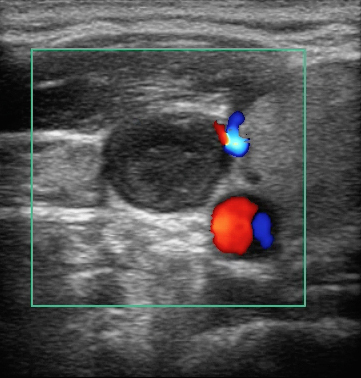

Imagen de trombo en la vena yugular